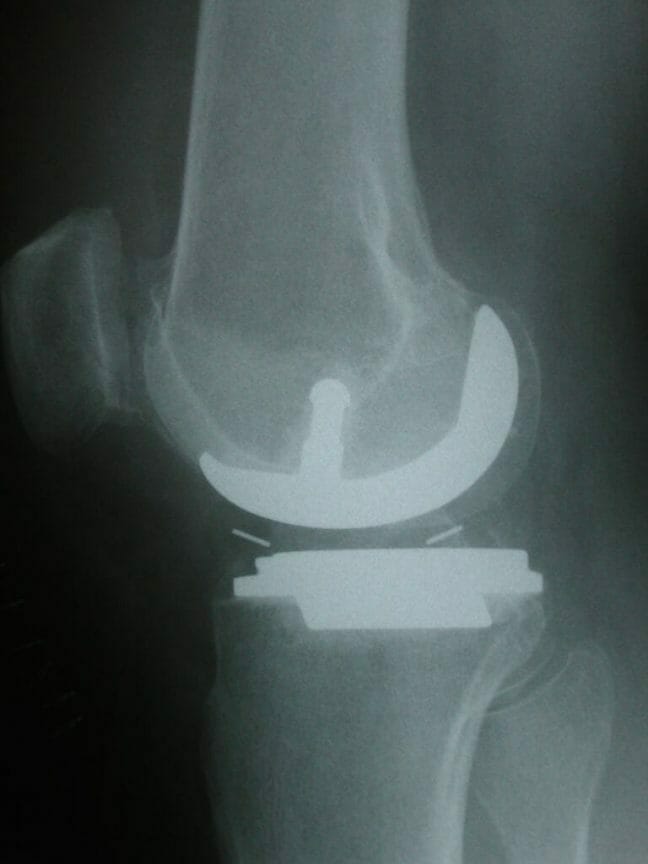

Investigations for arthritis usually entail weight-bearing radiographs of the knee and also a long leg standing alignment x-ray of the leg to show the axes of the leg and knee.

AP x-ray of the knee showing gross lateral compartment osteoarthritis with total loss of lateral joint space.